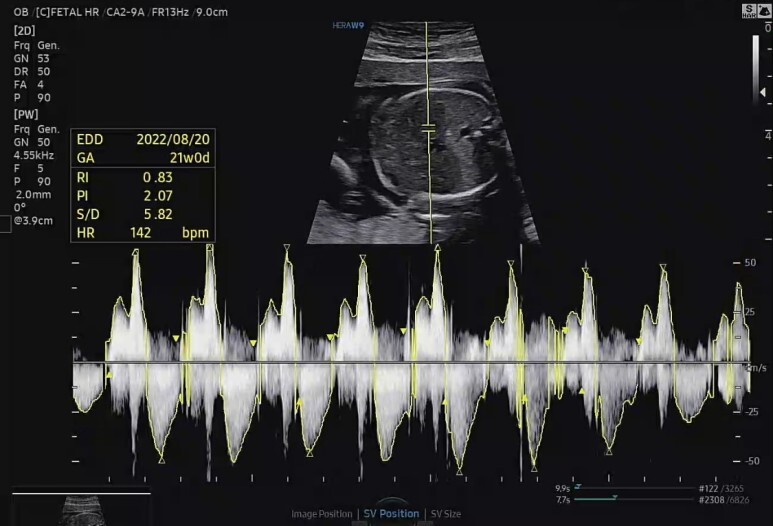

심박수.

HR 142 bpm